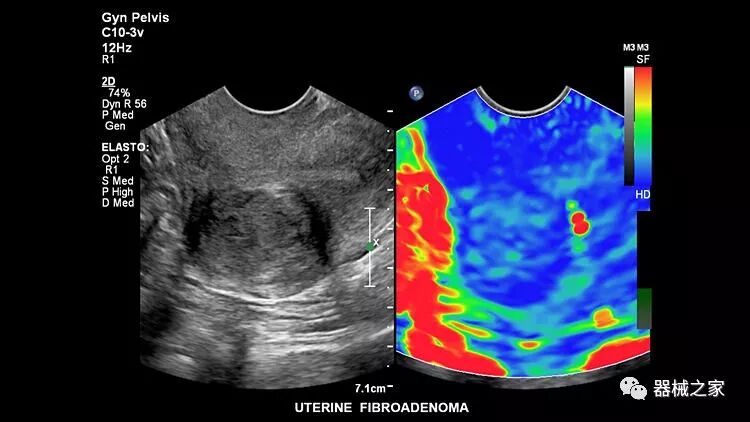

在几年前,超声波无法对小型慢流血管中的血流进行成像,但现在有少数供应商提供具有此功能的系统。该特征提供了另外一种检查病变以指示癌症或炎症的方法。其中一个是佳能Aplio 900 CV系统,它可以显示毛细血管中的血流量。日立的Arietta 65中程系统提供了一种可视化小血管的功能,可以更好地观察肾脏等器官的灌注情况。三星RS85还提供MV-Flow可视化慢流微血管结构。